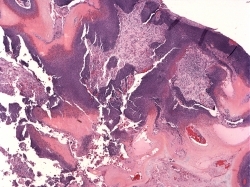

Fig 2 Porphyria cutanea tarda. Scanning view of a subepidermal blister.

Fig 3 Porphyria cutanea tarda. The blister cavity is cell free. Note the festooning.

Fig 4 Porphyria cutanea tarda. The presence of erythrocytes in the lumen of the blister is a common finding.

Fig 5 Porphyria cutanea tarda. The blood vessels are thickened, and there is a background of solar elastosis.